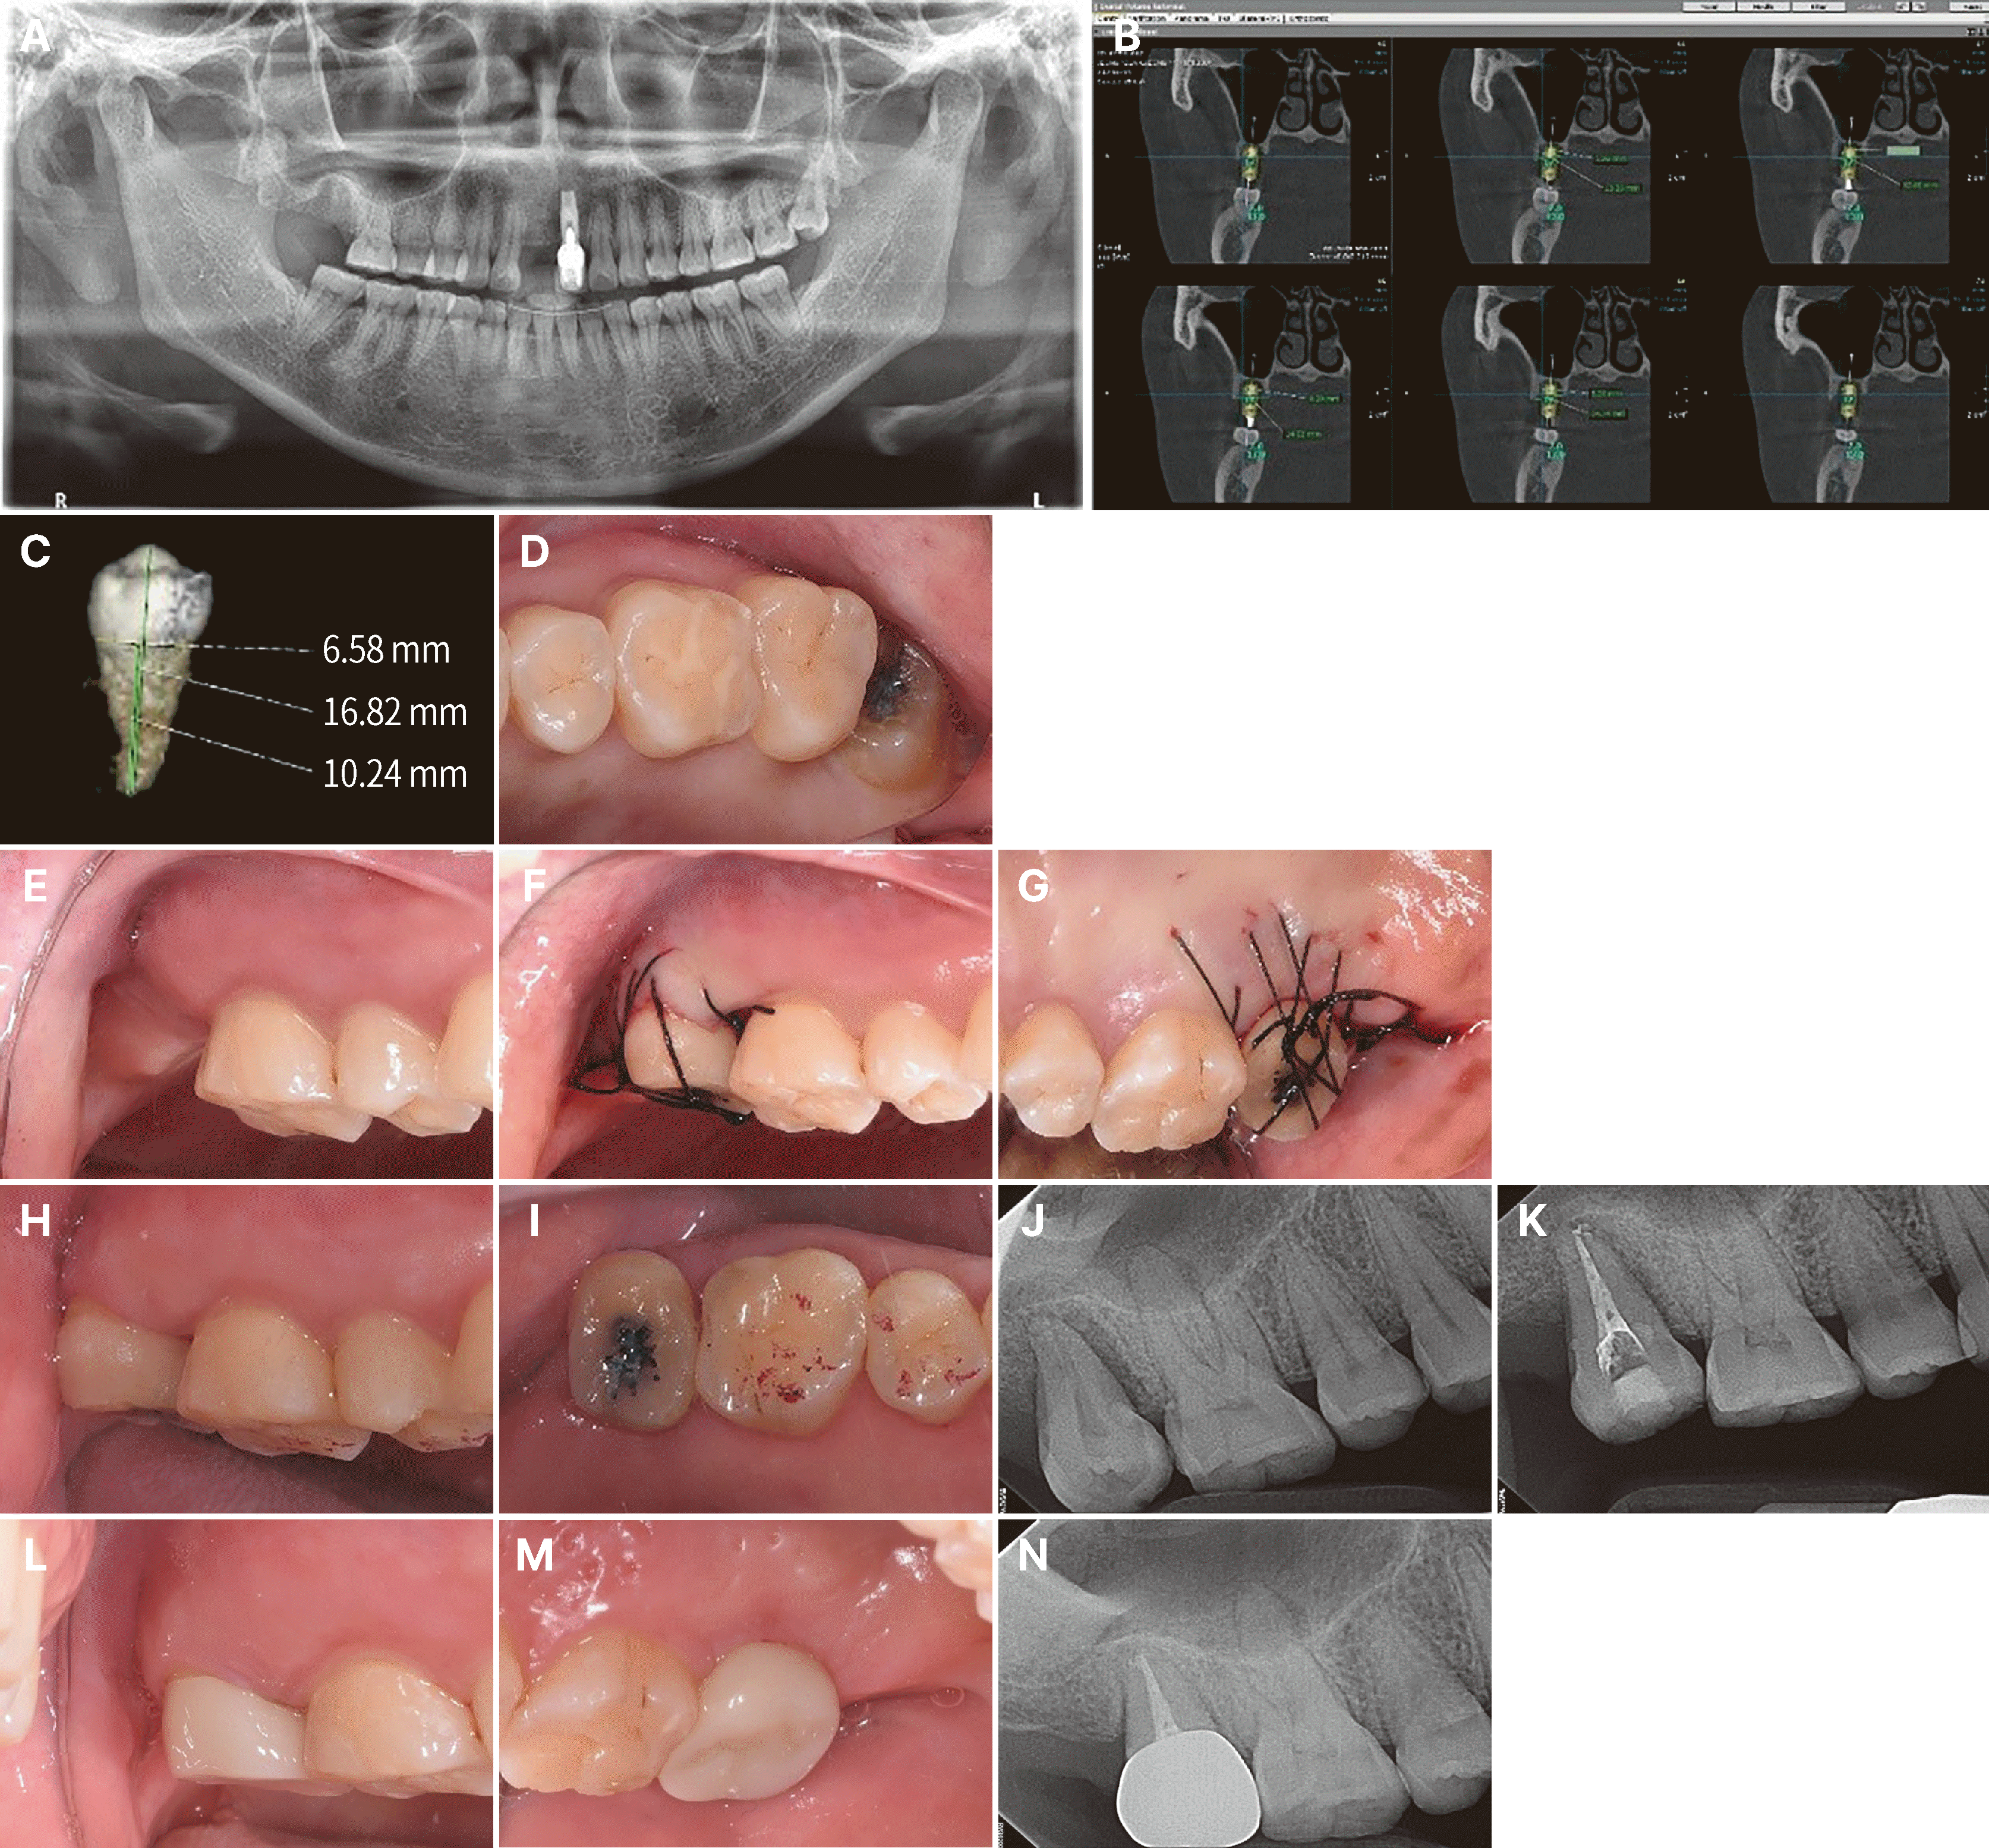

39세 여자가 보존과에서 상악 우측 제2대구치와 중절치가 발치된 후 임플란트 치료를 위해 치주과로 의뢰되었다. 환자는 당뇨 및 고혈압으로 약물복용 중이었다. 상악 우측 제2대구치가 2021년 5월에 근관 치료 및 수복되었고 2024년 6월 치근 파절로 발치되었다(Fig. 1A). 2024년 7월 초에 상악 우측 제2대구치와 중절치에 임플란트 식립을 계획하여 해당 부위 스텐트를 장착하고 CBCT (CS 9300; Carestream Health Inc., Rochester, USA)를 촬영하여 분석하였다(Fig. 1B). 상악 우측 중절치는 임플란트 식립하기로 계획하였고 상악 좌측 제3대구치는 제2대구치의 원심부로 근심 경사되어 있고 교합면에 상아질 치아우식증이 존재하여 발거가 필요하였고 치근 모양이 tapered되어 있어 자가치아이식에 적절할 것이라고 판단하여 시행하기로 결정하였다(Fig. 1C, 1D). CBCT Dicom 파일을 Ondemand 3D (Cybermed, Seoul, Korea)를 이용하여 공여치아(상악 좌측 제3대구치)의 예상 모양을 재구성하여 3D printing을 시행하여 모형을 제작하였다.

2024년 12월, 수술부위에(Fig. 1E) 국소마취를 시행하였고 상악 우측 제2대구치 부위가 발치된 후 약 6개월이 경과하여 골과 연조직의 치유가 거의 완성되었기 때문에 판막을 형성한 후 생리식염수 주수 하에 low-speed 드릴(round bur와 임플란트 골삭제 버)을 이용하여 골 삭제를 시행하여 수여부를 형성하였다. 수여부의 형성을 용이하게 하기 위해 술전에 치아 모형 치경부의 외형에 맞게 wire를 접어 소독하였다. 골 삭제는 먼저 접어놓은 wire를 치조골에 놓아 외형을 확인한 후 표시하고 4 mm round bur로 삭제하였다. 그리고 길이가 표시된 임플란트 골삭제 버를 이용하여 길이에 맞게 삭제하였다. 치아 모형을 이용하여 적합성을 평가하면서 수여부를 조정하였다. 공여치아인 상악 좌측 제3대구치를 periotome (Hu-Friedy, Chicago, USA)과 발치겸자를 이용하여 조심스럽게 발치하였다. 수여부가 발치 후 치유 과정 중 골흡수가 있었고 반대측의 공여치아이고 치근이 원심측으로 구부러져 있으므로 공여치아의 협설측을 반대로 하여 수여부에 시적하여 적합성 확인후 방사선 촬영하였다. high-speed 다이아몬드 버를 이용하여 이식된 치아가 교합되지 않게 하기 위해 공여치아의 교합면을 삭제하였고 고정 봉합을 위해 봉합사가 미끄러지지 않게 협설 교두 부위에 indentation을 형성하였다. 그리고 봉합사(4-0 Mersilk; Ethicon, Johnson & Johnson, New Brunswick, USA)로 수여부의 판막을 긴밀하게 봉합하였고 cross suture를 이용하여 봉합사로 치아를 고정하였고(Fig. 1F, 1G) 치주팩(COE-PAK, GC Europe NV, Leuven, Belgium)을 위치시켰다. 적절한 항생제(아목시실린, tid)를 3일간 구강 투여하도록 하였고 0.12% 클로르헥시딘(헥사메딘액, 부광약품, 서울, 한국) 린스하도록 지시하였다. 봉합사와 치주팩을 1주일 후에 제거하였다. 치근 완성된 치아의 경우 자가치아이식 후 근관치료가 꼭 필요하며 2주 이후에 시작되고 4주까지는 근첨부까지 치수조직을 제거해야 한다고 Tsukiboshi 등이 제시하였다.11 자가치아이식 시행 후 2주 후에 치아의 움직임이 거의 없어 근관 치료를 시행할 수 있을 것으로 판단되어 보존과로 의뢰하였다(Fig. 1H, 1I, 1J). 다음날 보존과에서 one-day 근관 치료가 시행되었다(Fig. 1K). 술후 3개월, 6개월 follow-up 시행하였다. 수술 6개월 후 자가이식된 치아는 임상적, 방사선학적으로 양호한 결과를 얻었다(Fig. 1L, 1M, 1N).

Fig. 1

A transplantation of a left maxillary third molar to right maxillary second molar site. (A) A panoramic view of a 39-year-old female, who was referred for the implant therapy of edentulous area. (B) CBCT image of right maxillary second molar site. (C) The 3D image of the left maxillary third molar from the DICOM data of the CBCT images. (D) Clinical occlusal view of the left maxillary third molar. (E) Preoperative state of recipient site. (F) Buccal view showed that the donor tooth was placed into prepared socket after suture. (G) Palatal view after suturing. (H) Clinical buccal view 2 weeks after surgery. (I) Occlusal view 2 weeks after surgery. (J) A periapical radiograph after 2 weeks. (K) A periapical radiograph after endodontic treatment. (L) Clinical buccal view after zirconia crown restoration. (M) Palatal view after crown restoration. (N) A periapical radiograph after transplantation 6 months later.